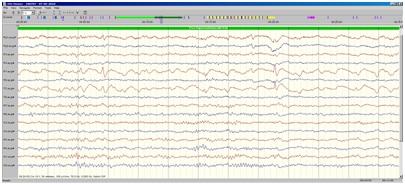

De små strømme kan give synlige udslag, og vises på en skærm. Tidligeret skrev man med penne på en kørende papirstrimmel, i dag er processen digital og stregerne vises på en skærm (fig. 1).

Fig. 1 Normalt EEG

Normalt EEG fra en voksen person. Midt i kurven (markeret gråt øverst i kurven)åbner patienten øjnene, og man ser her, især i de to nederste kanaler, at kurvebilledet ændrer sig fuldstændigt, kurven ”flader ud”, og den regelmæssige aktivitet (den såkaldte alfa-rytme) forsvinder; dette er en normal reaktion, når man åbner øjnene, eller foretager sig noget mentalt, f eks hovedregning).